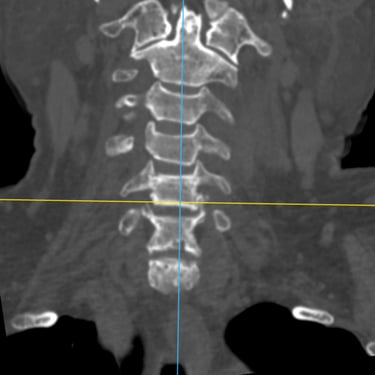

Discitis Cervical con Absceso: Descompresión Cervical y Artrodesis

La discitis cervical con absceso es una infección grave de la columna que puede comprometer el disco intervertebral, los cuerpos vertebrales y las estructuras neurológicas, generando dolor cervical intenso, fiebre y déficit neurológico progresivo. Cuando existe compresión medular o inestabilidad, el tratamiento quirúrgico mediante descompresión cervical y artrodesis es fundamental. Este procedimiento permite drenar el absceso, liberar la médula espinal y estabilizar el segmento afectado, favoreciendo el control de la infección y la recuperación neurológica. El manejo oportuno y multidisciplinario es clave para mejorar el pronóstico del paciente.